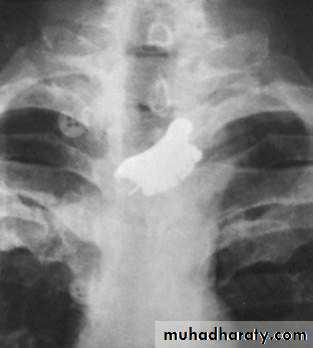

Is the most useful way to diagnose GERD (pH less than 4 for more than 4% of study time.Foreign bodies in the esophagus

The most common is food bolusThe most dangerous is button batteries in children.

Usually diagnosed by plain radiograph.

Either pass spontaneously or removed by OGD.

Figure 4: false teeth impacted in the esophagus.